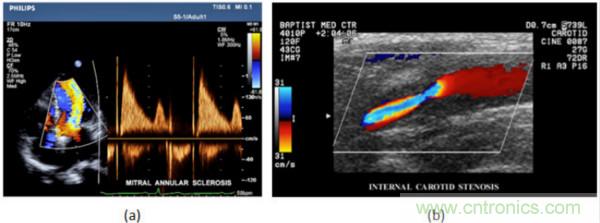

在CW和PW多普勒模式中,流信息是從一個聚焦聲束中獲得的,類似于A模式成像。在20世紀80年代,研究人員基于彩色多普勒技術(shù)完成了血流分布的二維信息可視化。彩色多普勒處理也是基于B模式/PW模式信號路徑。從感興趣區(qū)域收集多幀RF數(shù)據(jù)。由于感興趣區(qū)域中的血液流動導(dǎo)致圖像幀之間存在數(shù)據(jù)差異。相域中的自相關(guān)和時域中的互相關(guān)兩種算法可從RF數(shù)據(jù)中提取數(shù)據(jù)方差(即血流速度和方向信息):。根據(jù)預(yù)定義的顏色漸變條相應(yīng)地映射包括速度和方向的血流信息。通常,藍色和紅色代碼分別識別朝向和遠離換能器移動的血流。當(dāng)流速增加時使用更亮的顏色,反之亦然。顏色映射的2D分布始終疊加在B模式圖像上,以實時同時顯示個體解剖結(jié)構(gòu)和血流。它對于診斷心血管疾病,如血管閉塞和心臟瓣膜反流,極其有用。典型的彩色多普勒圖像如下圖所示,(b)顯示頸動脈狹窄引起的血流流速變化。

圖7.彩色多普勒成像:(a)以彩色多普勒和CW模式獲得的圖像(由Philips提供); (b)顯示頸動脈狹窄的彩色多普勒(由GE提供)